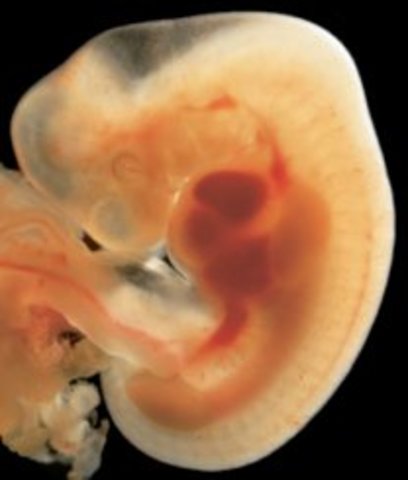

• Week Ten: Embryo is now a Fetus

Week Ten: Embryo is now a Fetus

The developing organism is called a fetus.It is the size of a small strawberry.